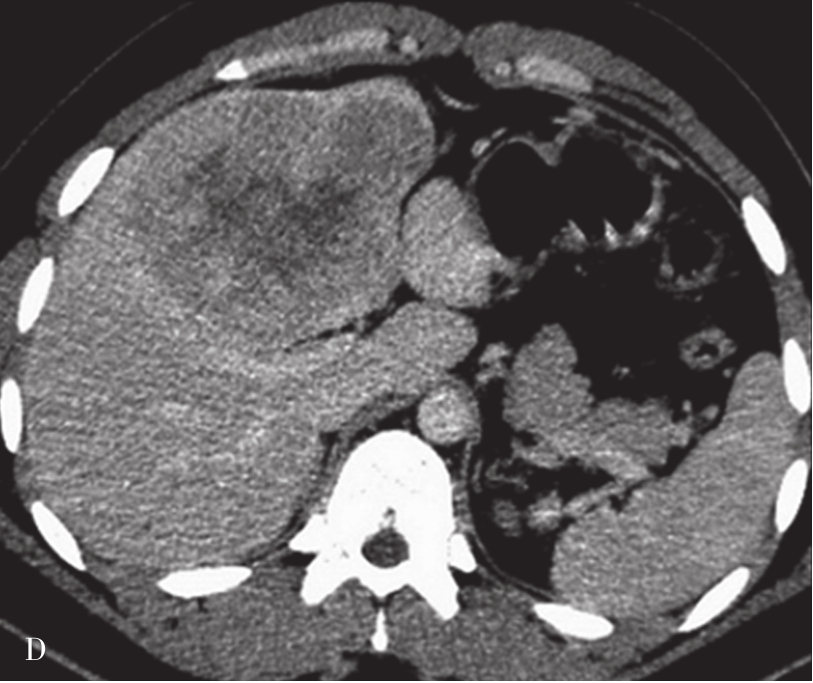

(2)CT表现:

巨块型和结节型平扫表现为单发或多发、圆形、类圆形或不规则形肿块,呈膨胀性生长,绝大多数肝癌边缘有假包膜,因而多数瘤灶边界清楚,这是肝细胞癌CT诊断重要征象;弥漫型者结节分布广泛,境界不清;小肝癌表现为肝实质内3cm以下类圆形肿块。肿块多数为低密度,少数表现为等密度,或在脂肪肝背景衬托下可呈高密度。巨块型肝癌可发生中央裂隙状坏死而出现更低密度区,合并出血或发生钙化,则肿块内表现高密度灶;有时肿块周围出现小的结节灶,称为子灶。多数肝癌主要由肝动脉供血,增强扫描动脉期,病灶通常出现明显的斑片状、结节状早期强化;在门静脉期,门静脉和肝实质明显强化,而肿瘤无或仅少量门静脉供血则强化程度迅速下降;平衡期,肝实质继续保持较高程度强化,肿瘤强化程度则继续下降而相对低密度表现,增强过程表现典型的“快进快出”的特征性改变(图5-21-38)。少数肝癌为门静脉供血为主者,其强化方式相对不典型。如在动态CT系列图像上分别测定CT值并绘制时间-密度曲线,可见肝癌强化的时间-密度曲线呈速升速降形曲线。肿瘤的假包膜一般呈延迟强化表现。有门静脉、肝静脉或下腔静脉癌栓者则增强门脉期或静脉期出现静脉内低密度充盈缺损,部分患者可见转移性腹膜后和肝门区的淋巴结肿大,以及远处转移。

图5-21-38 HCC患者的CT平扫及增强图像

A.CT平扫图像,肝右前叶内可见巨块状稍低密度影,大小约10.5cm×8.3cm,CT值为36~46HU,其内密度不均,界限欠清,病灶内可见更低密度影;B.增强扫描动脉期,病灶不均匀强化,CT值约69HU,并见多量小刷状不成熟肿瘤血管影(箭头);C.增强扫描门脉期图像,病灶密度略低于肝脏实质,CT值约68HU,病灶假包膜厚薄不均(箭头);D.3min延迟期图像,随着时间的延长,病灶密度低于肝脏实质,CT值64HU,中央低密度区未见明显强化;E.动脉期最大密度投影法重建图像示肝动脉分支明显增多供应病灶